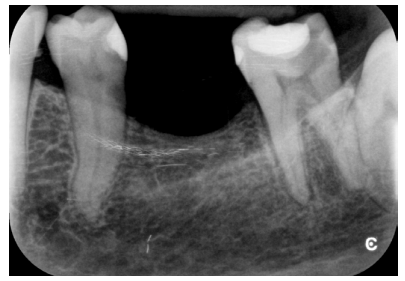

La paciente no presentaba antecedentes médicos de interés. En la exploración clínica (Figura 1) se observó que el 3.7 presentaba una lesión cariosa extensa, correspondiendo a un valor ICDAS 6, y una restauración oclusal previa de composite. En la exploración radiográfica (Figura 2) no se apreciaba banda de dentina entre la lesión cariosa y la cámara pulpar. Por tanto, según la clasificación clínico-radiográfica del International Caries Classification and Management System (ICCMS®) 4 se considera una lesión de caries severa. Presentaba un ligero ensanchamiento del espacio del ligamento periodontal en la raíz mesial y lesión apical. Se realizaron las pruebas de diagnóstico pulpar y periapical pertinentes (Tabla 1). El diagnóstico pulpar fue pulpitis irreversible sintomática y el diagnóstico periapical fue periodontitis apical sintomática.